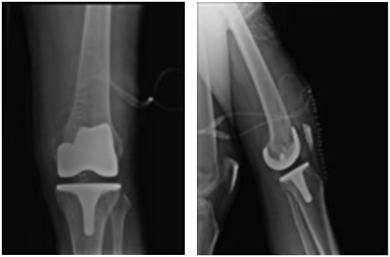

A cemented left total knee replacement was performed. Degeneration was observed throughout the knee, with loss of articular cartilage involving the medial and lateral compartments. A black pigment was deposited throughout the articular cartilage (Fig. 3 ). The postoperative radiographs showed that the total knee components were in good alignment and position (Fig. 4 ). The patient progressed well postoperatively, maintaining a good range of motion and achieving independent ambulation 4 weeks after surgery. At the 10-year follow-up, the patient had returned to full activities, reported no knee pain, and was very satisfied with the outcome. No abnormality of the femoral, tibial, and patellar components was observed in the plain x-rays taken 10 years postoperatively (Fig. 5 ).

Fig. 4

Fig. 4.

Radiographs following total knee arthroplasty.

Fig. 5

Fig. 5.

Anteroposterior and lateral radiograph of same knee at 10th year postoperatively, with stable components.